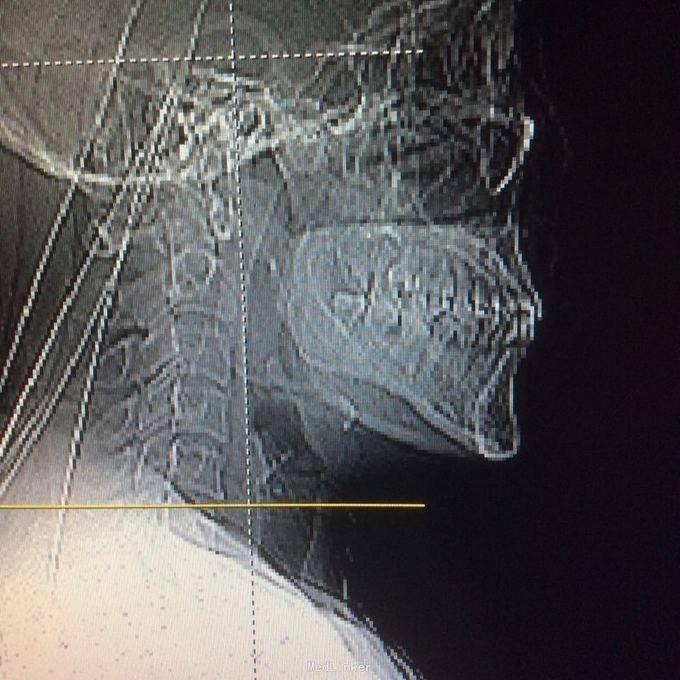

压头及右侧臂丛牵拉试验阳性,无明显浅感觉减退,右上肢肱三头肌肌力2级,双上肢腱反射活跃,双上肢病理征阳性 颈椎ct见颈椎6、7水平后纵韧带骨化,继发相应的椎管水平狭窄,自带核磁见颈椎2-7间盘向后突出,硬膜囊前缘受压